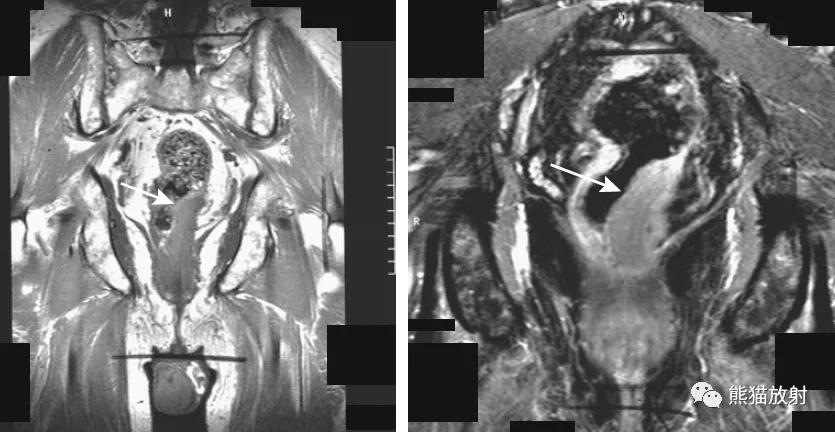

直肠癌。平扫和增强的冠状T1WI图像显示远端直肠左侧壁肿瘤(箭头)侵犯直肠周围脂肪。